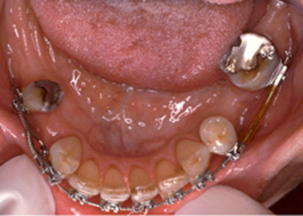

I Fig 2 ses ett djupt bett med multipla agenesier. Man ser en begynnande bettkollaps. Överkäksfronten har buckaltippat, överkäkens molarer som saknar antagonister har övererupterat och bettet djupnar alltmer. Behandlingsmålen i det här fallet var att häva det djupa bettet, skapa stabila stödzoner och en frontal avstödning och styra platsöverskottet för tandersättningar i sidopartierna.

Här gjordes distalföring av premolarer i underkäken med miniimplantat som förankring. 45 och 34 distalflyttades 6-7mm och goda ocklusionskontakter skapades mot överkäks-6:orna. I det här fallet var terapivalet implantat som tandersättningar, men principen är densamma som när tänder distalförs inför tandstödda broar.